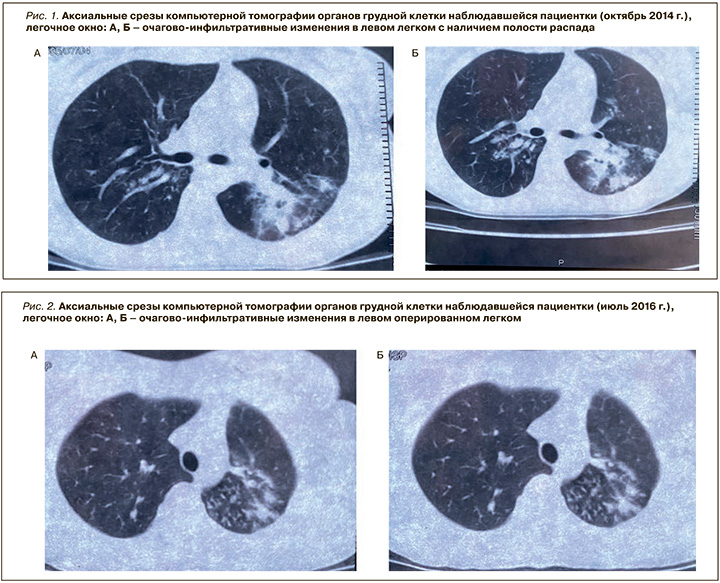

Анамнез заболевания: наличие хронических заболеваний пациентка отрицает. Туберкулезом болела в 2014 г., получала лечение в противотуберкулезном диспансере (ПТД) по месту жительства. Наблюдался инфильтративный туберкулез в фазе распада МБТ (+) при сохраненной лекарственной чувствительности возбудителя (ЛЧ МБТ); в течение 8 мес. проводилось лечение по 1-му режиму химиотерапии, на фоне которого сформировался фиброзно-кавернозный туберкулез левого легкого (рис. 1).

Несмотря на сохранение активности специфического процесса по данным МСКТ ОГК, спустя 8 мес. лечения в ПТД по месту жительства пациентке было выполнено оперативное лечение в следующем объеме: видеоассистированная торакоскопия (ВАТС) слева, резекция S1–S2, S6 левого легкого. Далее М. получала сезонные противорецидивные курсы противотуберкулезной химиотерапии, в 2015 г. было достигнуто клиническое излечение. Однако в 2016 г., спустя год после оперативного лечения, при проведении МСКТ ОГК у пациентки визуализировались «свежие» очагово-инфильтративные изменения в левом легком (рис. 2).